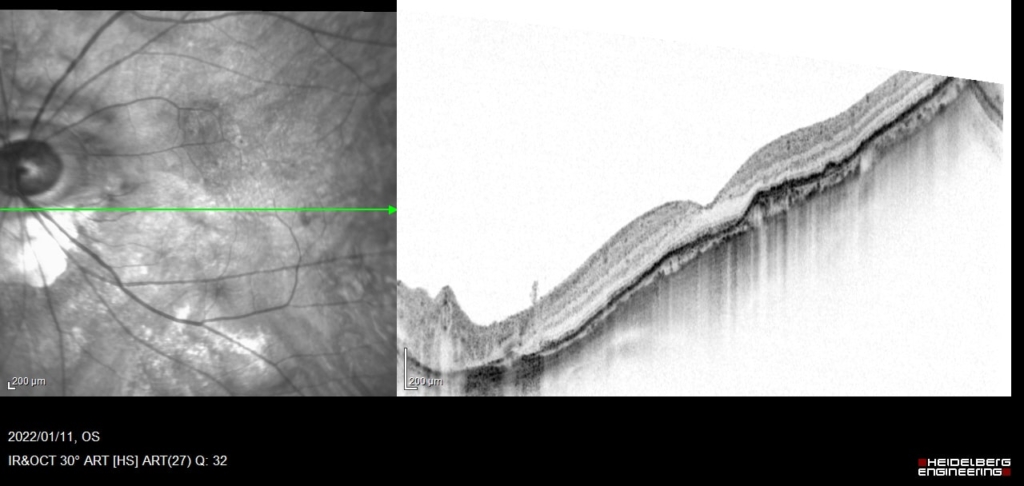

RPE下に広がるCNVとBruch膜の間に間隙が生じており、同部位でBruch膜が後方に偏位している。間隙は浸出液の貯留による。

4wで硝子体注射

間隙は縮小しているが、PED全体は増大している。